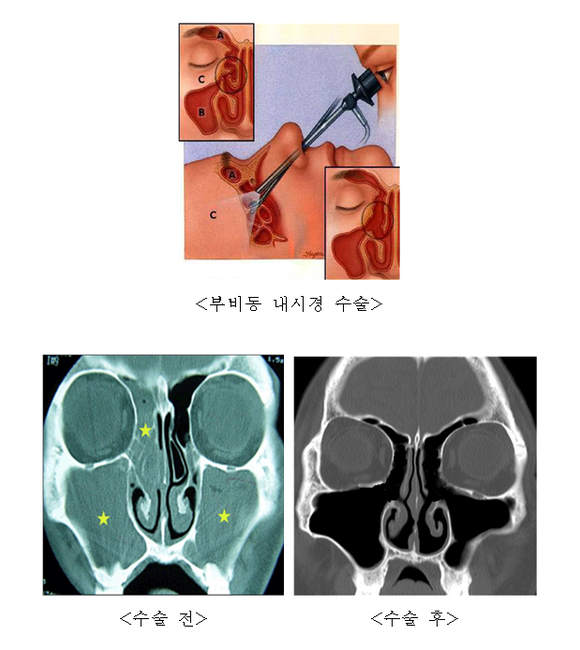

과거에는 입술을 들고 내부의 점막을 절제해 부비동에 접근하는 수술 방식이 사용됐다. 그러나 이 수술방법은 재발율이 50%에 이르러 부비동염 수술은 재발이 잘 된다는 인식이 많았다.

하지만 최근에는 내시경을 이용해 염증이 있는 부비동을 개방하고 환기와 배설을 용이하게 하여 물혹 등 비정상적 부비동 조직을 제거하는 내시경 수술이 도입되어 환자의 수술 만족도가 크게 향상됐다. 또한 비강과 부비동의 정상적인 점막은 남겨놓기 때문에 재발율도 과거에 비해 현저히 줄어들었다.

과거에는 부비동염 진단을 위해서 X-ray 촬영을 하고 얼굴 안쪽 부비동의 음영의 혼탁 정도로 진단했으나 현재 축농증의 진단과 병의 정도를 알아 보기 위해서 CT 촬영 및 비내시경을 사용한다.